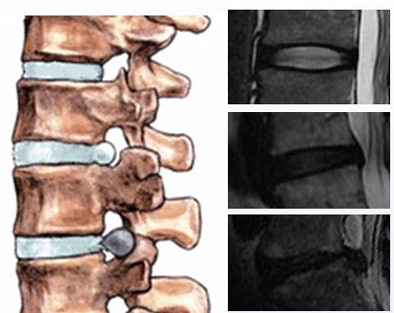

| Intervertebral disk herniation is seen in the localized displacement of disk material beyond the limits of the intervertebral disk space -- either protrusion or extrusion. All images courtesy of Sofia Michopoulou. |

MRI is nearly ideal as a diagnostic tool for intervertebral lumbar disk herniation due to its excellent soft-tissue contrast, which enables precise delineation of the disk borders, said Michopoulou in a Friday presentation at the Computer Assisted Radiology and Surgery (CARS) meeting in Geneva.